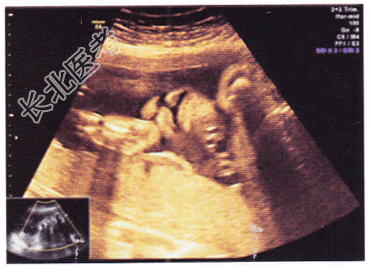

- 单项选择题胎儿超声检查如图,以下最可能的诊断是

A、正常声像图

B、唇裂

C、下腭裂

D、淋巴管囊肿

E、以上腭裂